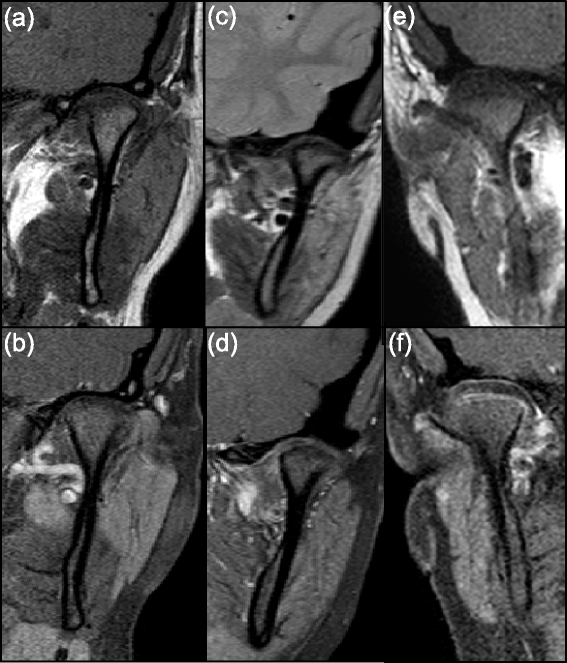

Methods: TMJ MRI examinations in 67 children with JIA and in 24 non-rheumatologic children who underwent MRI for neurologic/orbit indications were retrospectively assessed. As a priori determined TMJs of JIA patients were categorized into three groups by experienced staff radiologists based on the degree of synovial and condylar enhancement: no active disease (rheumatologic control), mild and moderate/severe findings. The signal intensity (SI) of the synovial tissue around each condyle and of the bone marrow was measured to calculate the enhancement ratio (ER) and relative SI change. The ER was calculated using signal to noise ratios, while relative SI change was calculated using signal intensities alone. Quantitative measurements of synovial and condylar enhancement of TMJs with mild or moderate/severe findings were compared with the rheumatologic and non-rheumatologic controls.

Results: Mean ER values were significantly different between the TMJs without active disease and those with mild and moderate/severe synovial enhancement, with highest values in the moderate/severe group (P < 0.0001). Similar findings were seen for condylar enhancement with P < 0.005. Relative SI change was unable to differentiate TMJs with mild synovitis from the two controls (P > 0.10). 27/60 (45%) TMJs without active disease had osteochondral changes. 8/40 (20%) TMJs in the mild group did not demonstrate any synovial thickening.